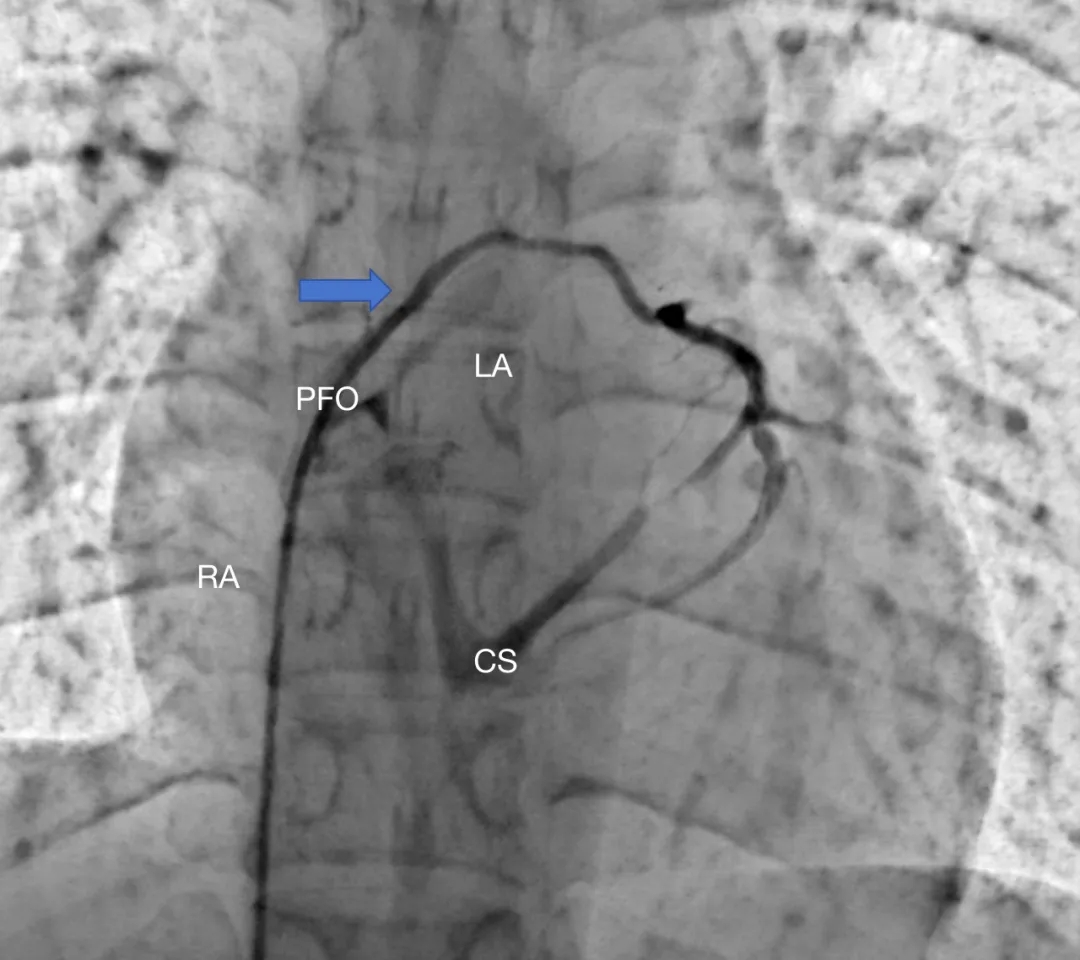

患者女性,27岁,因“卵圆孔未闭相关卒中”入院,拟行介入封堵术。术中MPA1导管跨越卵圆孔进入左心房后送入超滑导丝,发现导丝经由冠状静脉窦走行区回到右心房内,考虑导管进入异常通道,进一步造影可见一起自左心房前壁的冠状静脉分支血管沿房间隔水平横行走行,造影剂最终汇入冠状静脉窦,引流入右心房(图1&2,视频1&2)。该病情血液动力学类似冠状静脉无顶综合征/房间隔缺损,同期行右心导管测肺动脉平均压16mmHg,QP/QS=1.0,排除具有血液动力学意义的左向右分流。由于无法立刻明确单纯封堵PFO的收益与风险,遂终止手术先行完成心脏增强CT明确病变解剖情况,增强CT(图3&4)及重建结果(图5&6)与造影一致,可见一冠状静脉分支起自左心房并沿房间隔走行最终汇入冠状静脉窦。考虑到患者的临床症状可能与PFO以及该异常静脉均存在相关性,且尚不能明确单纯封堵PFO的收益以及同期封堵该静脉的风险,与患者充分沟通后暂时选择最优药物治疗并保持密切随访。

图1